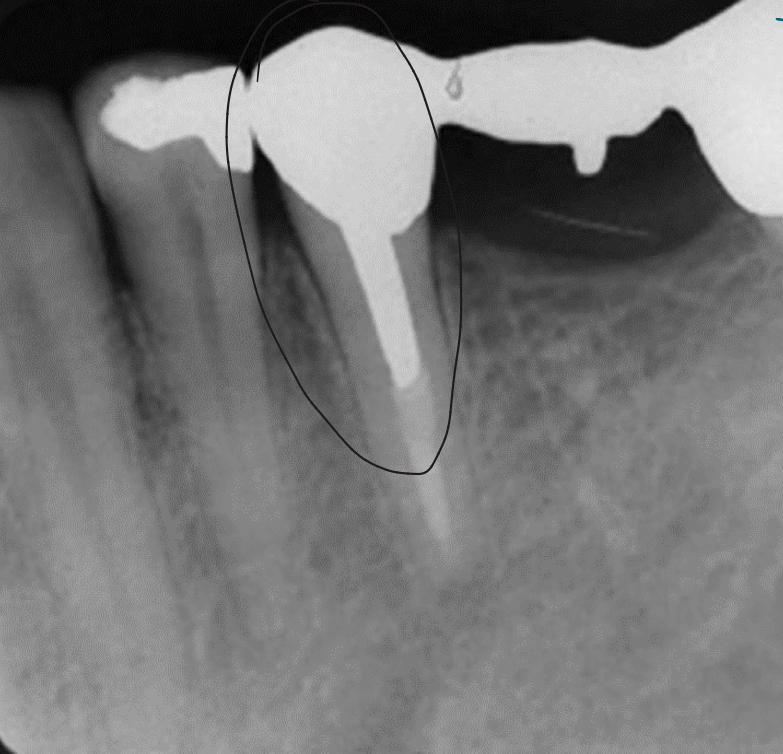

Unloaded implant

Implant loaded